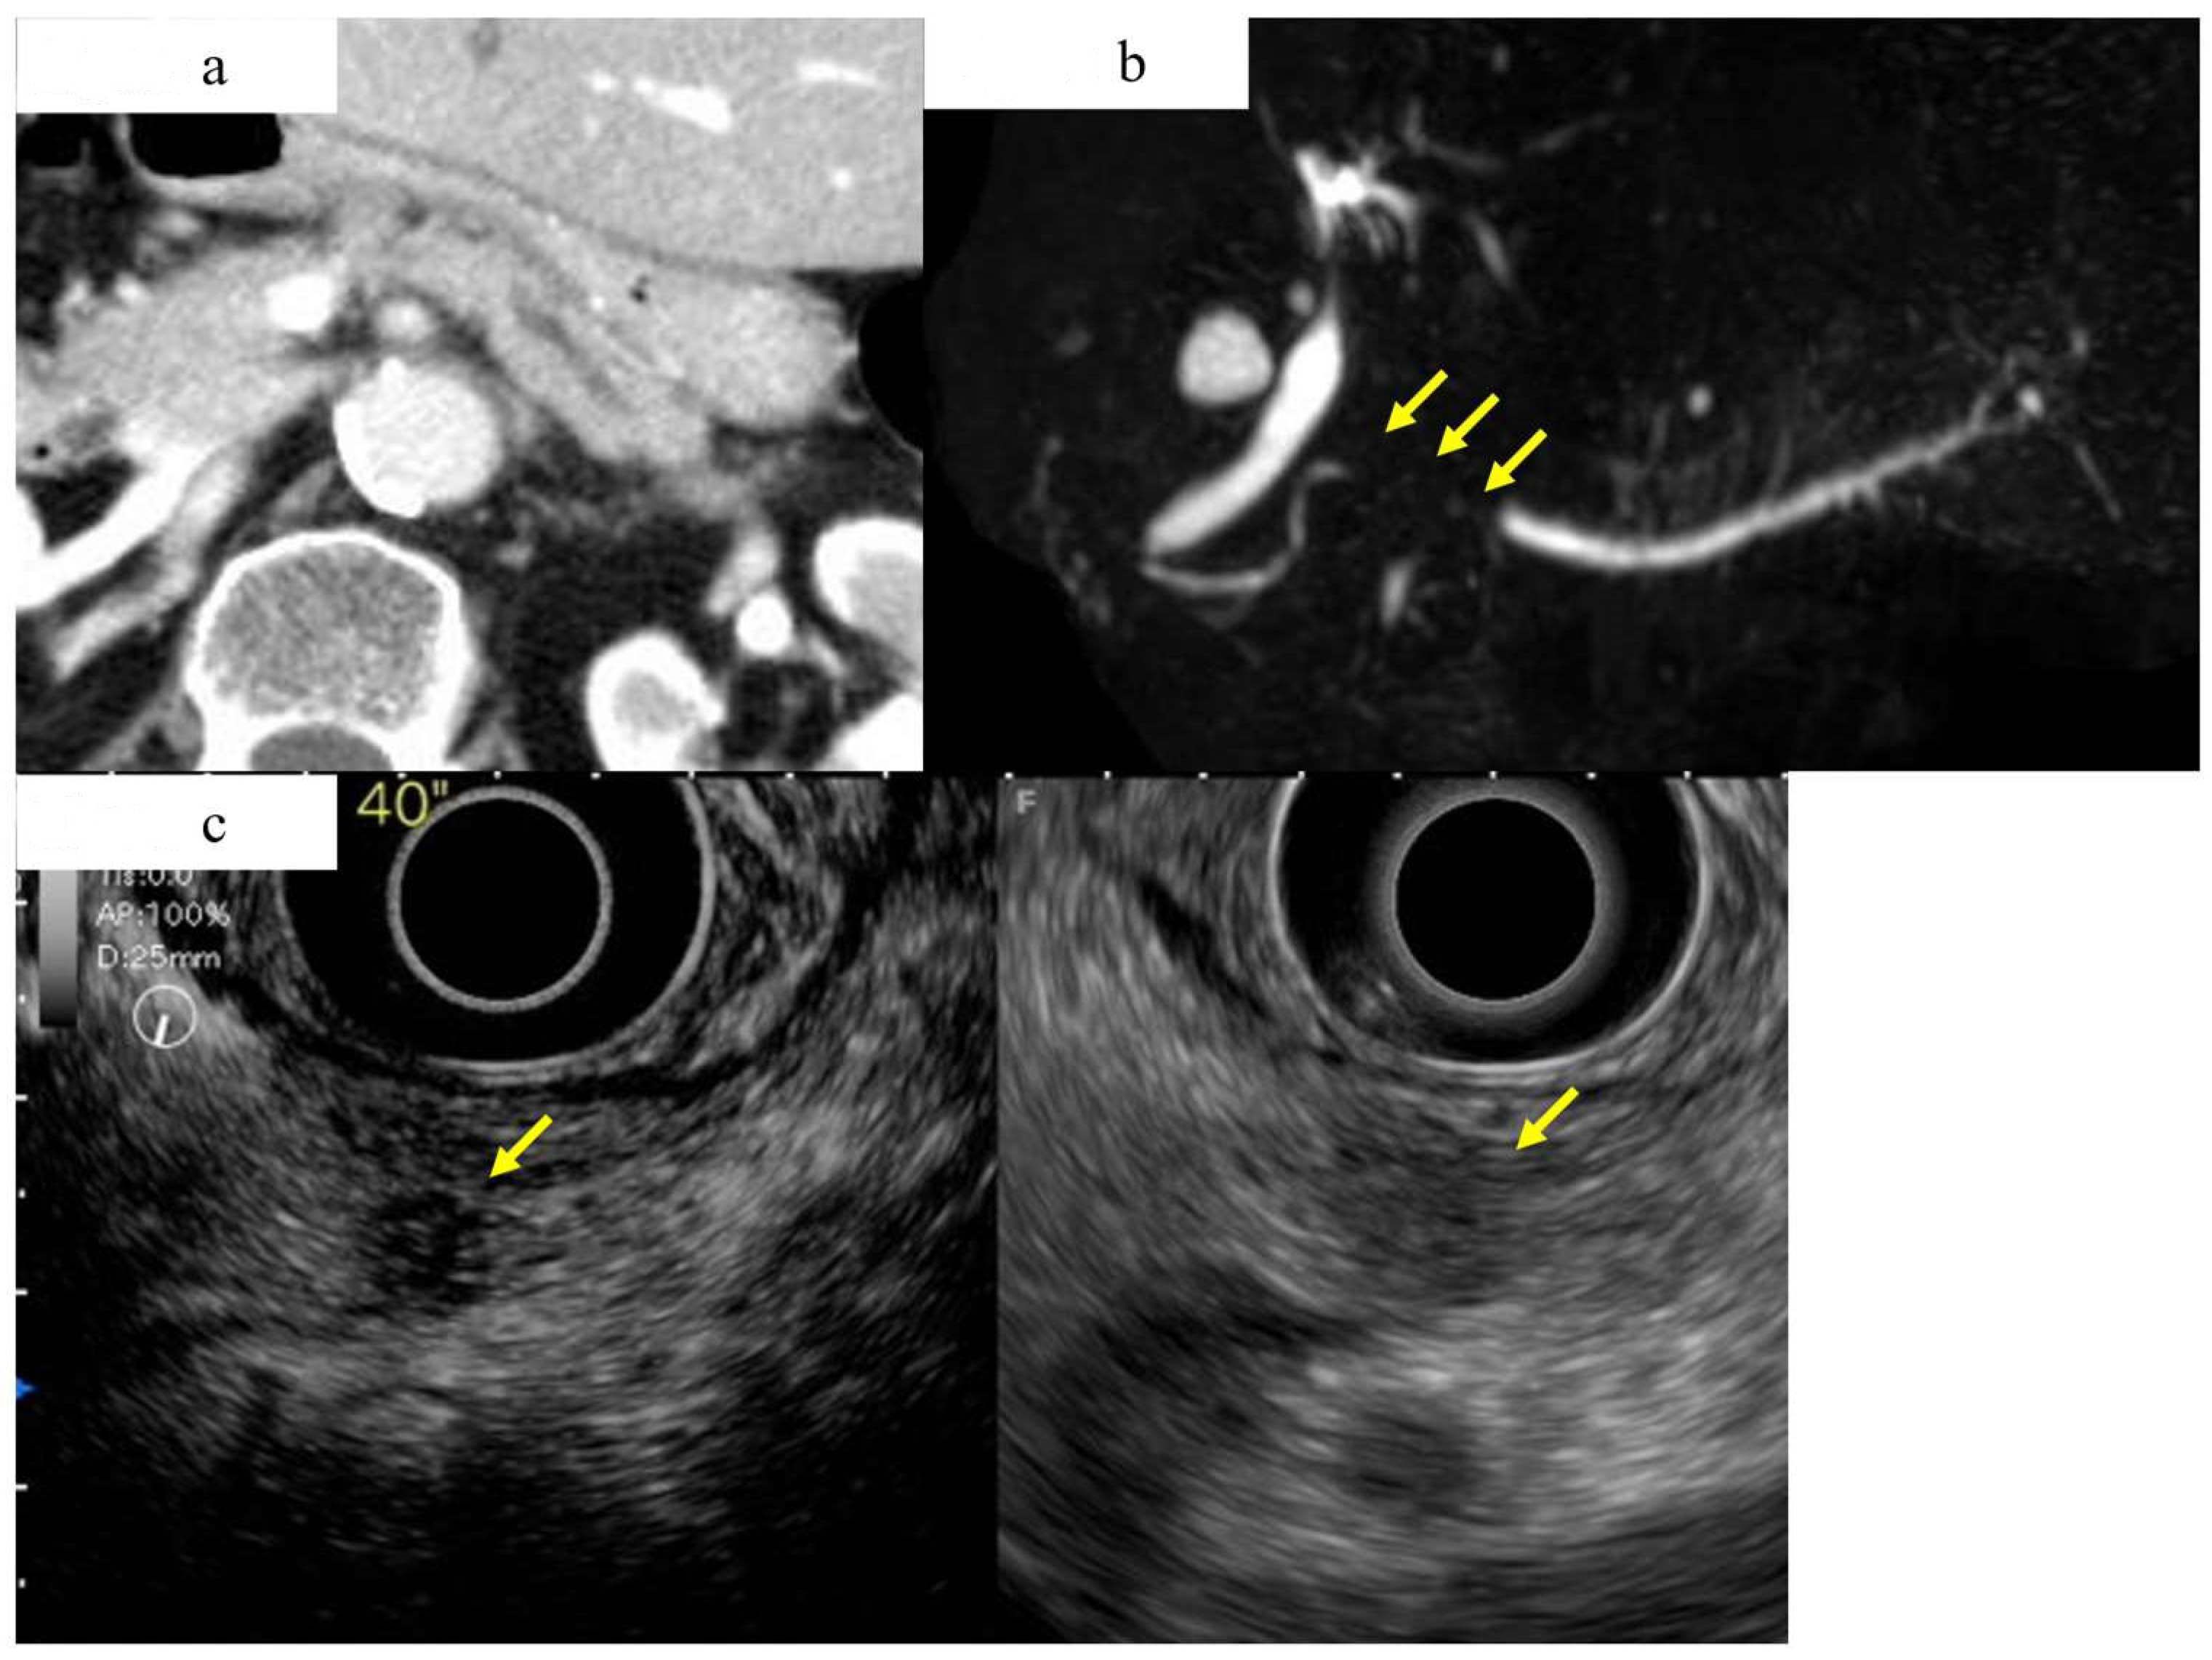

Figure 5.

A case of early-stage PDAC in the body in which CT and MRCP imaging studies did not show a pancreatic tumor, but an EUS study showed a pancreatic mass. (a) Contrast-enhanced CT showing mild dilation of the main pancreatic duct, but no obvious tumor was detected (yellow arrow). (b) Magnetic resonance cholangiopancreatography showing stenosis of the MPD (yellow arrow) and dilation of the MPD and branch ducts in the caudal part. (c) A hypoechoic lesion with a diameter of 8 mm (yellow arrow) was detected in the pancreas using fundamental B-mode EUS (right), and enhanced-EUS (left) revealed that the lesion (yellow arrow) had a lower echo signal intensity than the surrounding pancreatic tissue.